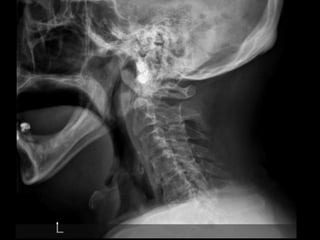

69 year old man with C2

fracture

Admitted for CHF and while

hospitalized was walking to

the bathroom at night and

fell on to head lacerating

forehead. Staff responded

to his calls for help and

immediately ordered a

cervical CT due to

complaints of new neck

pain

69 year oldman with C2 fracture Admitted for CHF and while hospitalized was walking to the bathroom at night and fell on to head lacerating forehead. Staff responded to his calls for help and immediately ordered a cervical CT due to complaints of new neck pain PMH: COPD, CHF, anxiety/dep, liver cirrhosis, cognitive decline, pulmonary HTN, SH: retired lives in group home